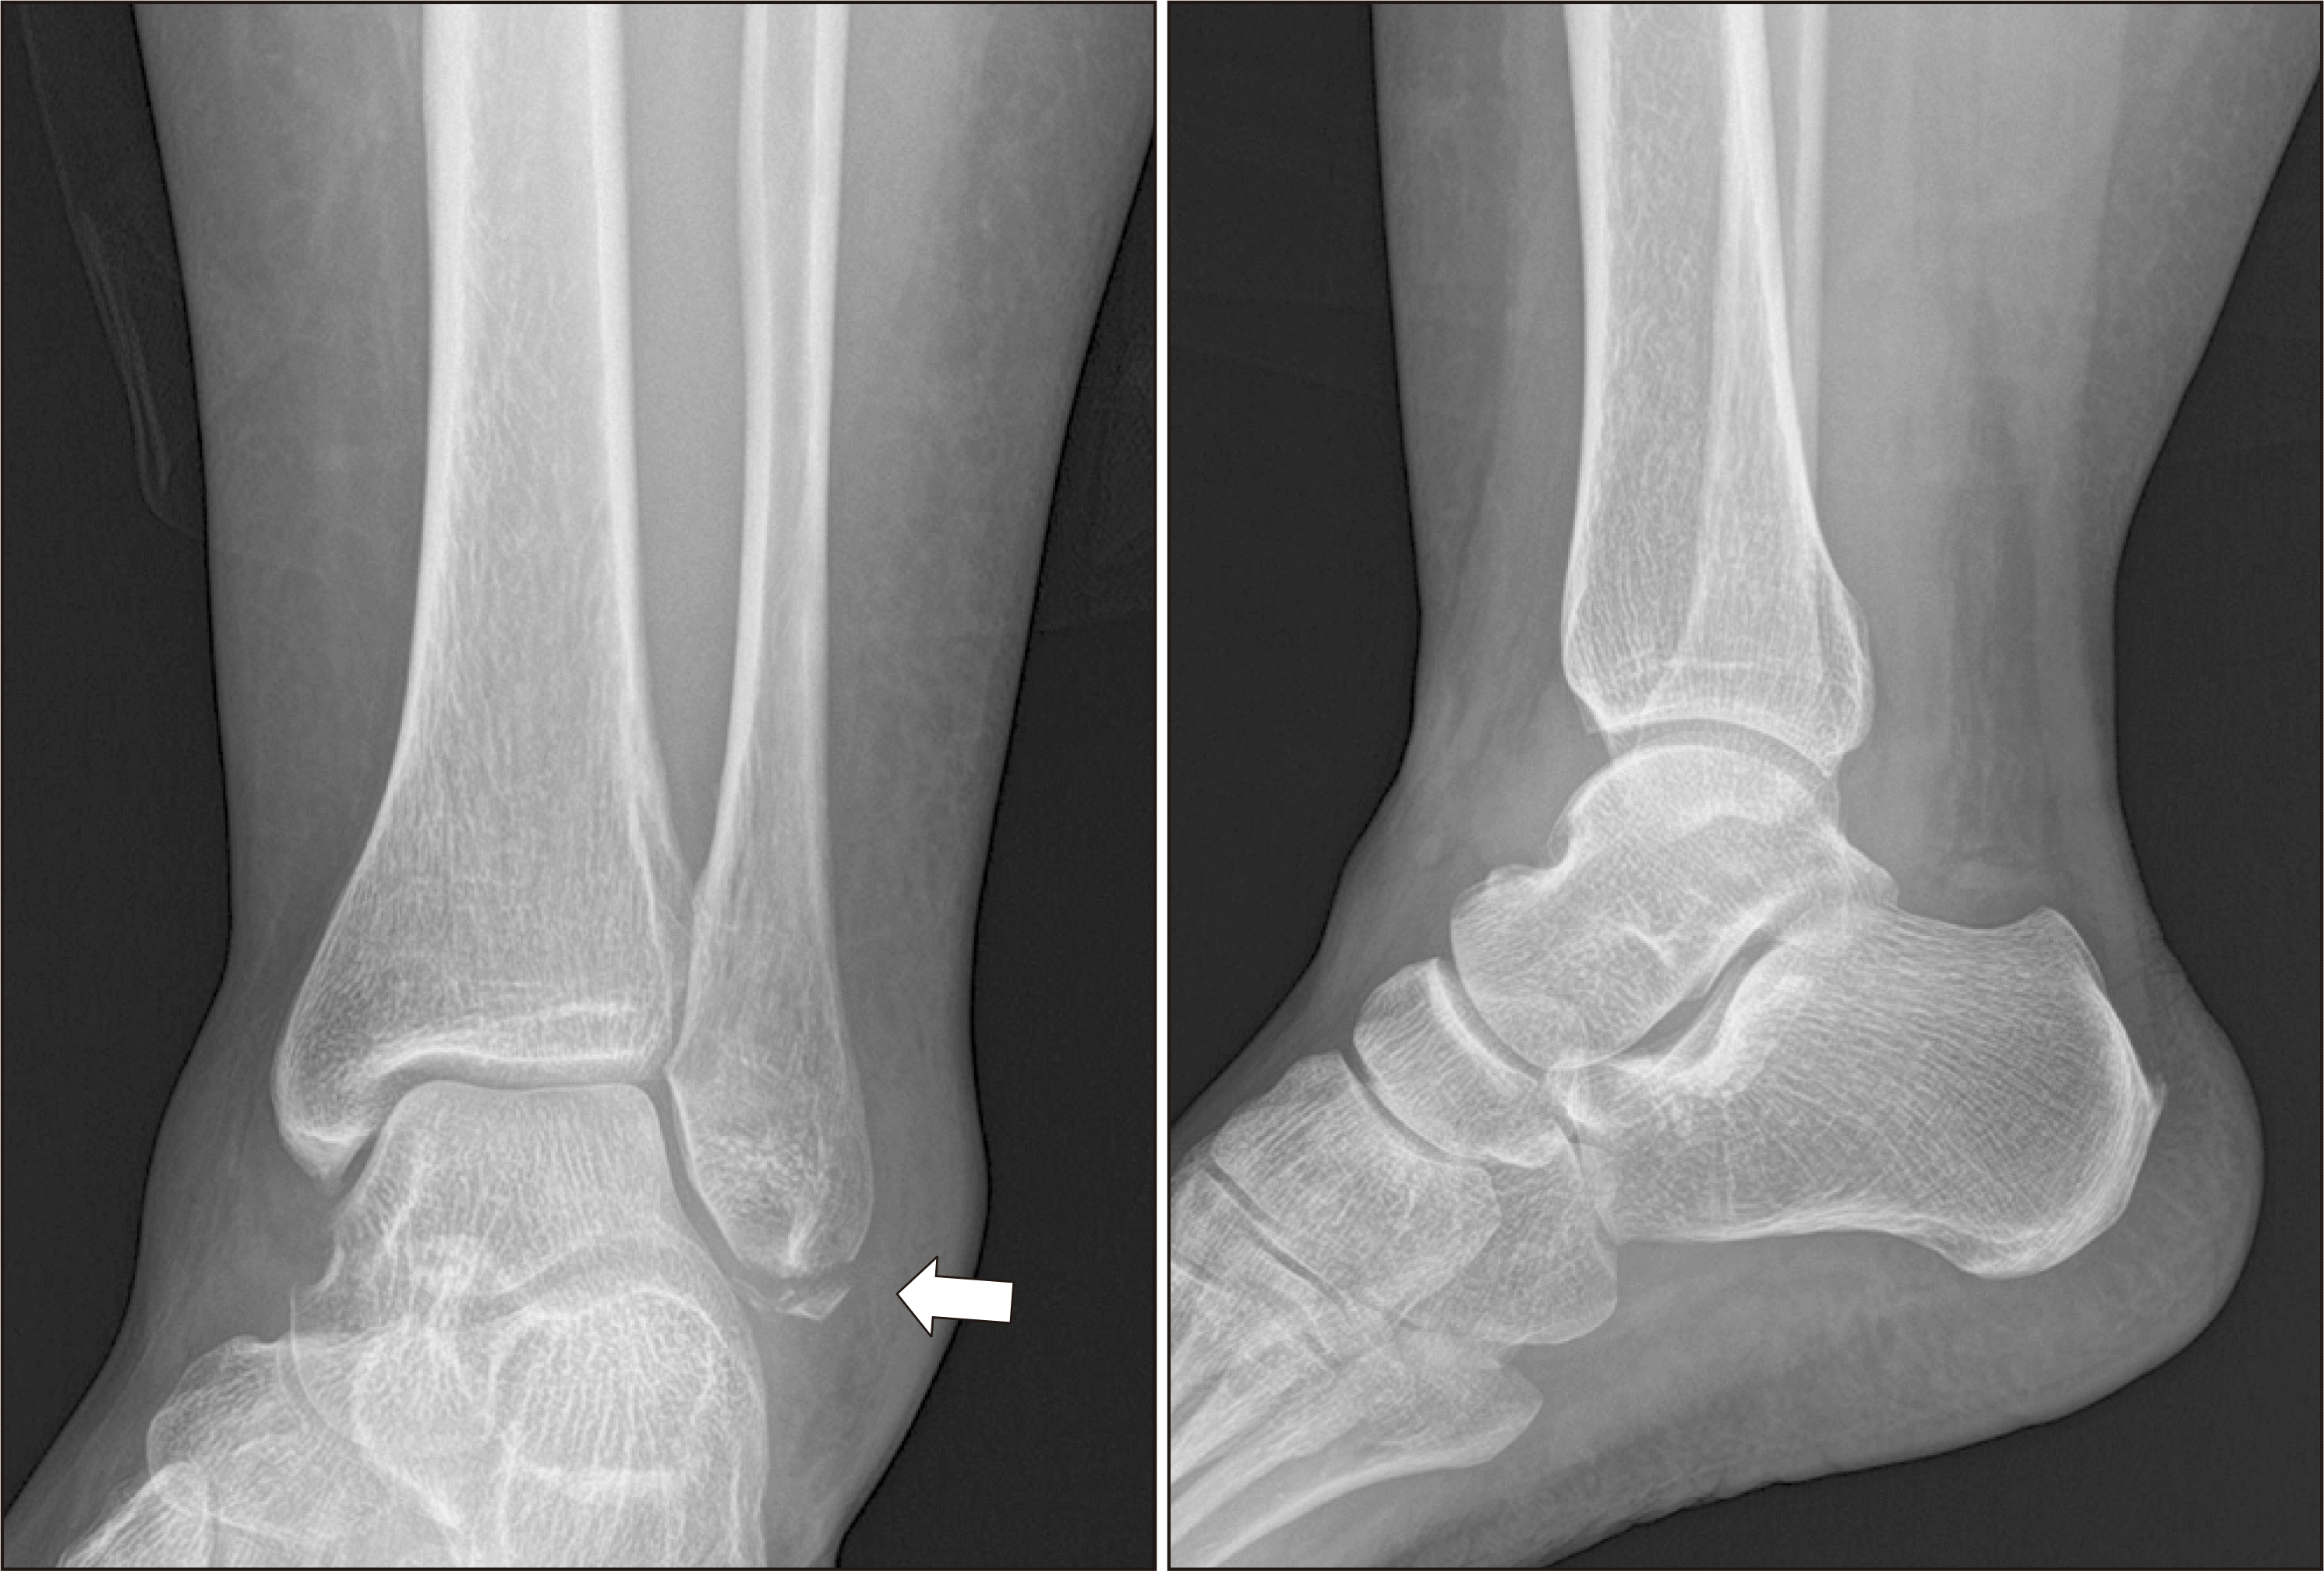

Figure 3

Postoperative radiographs of the left ankle show good reduction of the avulsed fracture fragment.